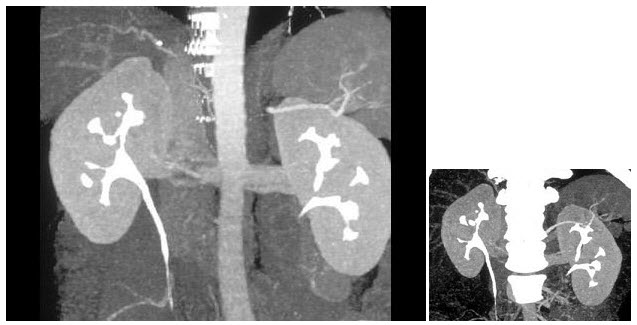

264、单项选择题

双肾CT平扫图像如下,符合下列何种疾病()

A.错构瘤

B.肾癌

C.肾囊肿

D.多囊肾

E.肾结石